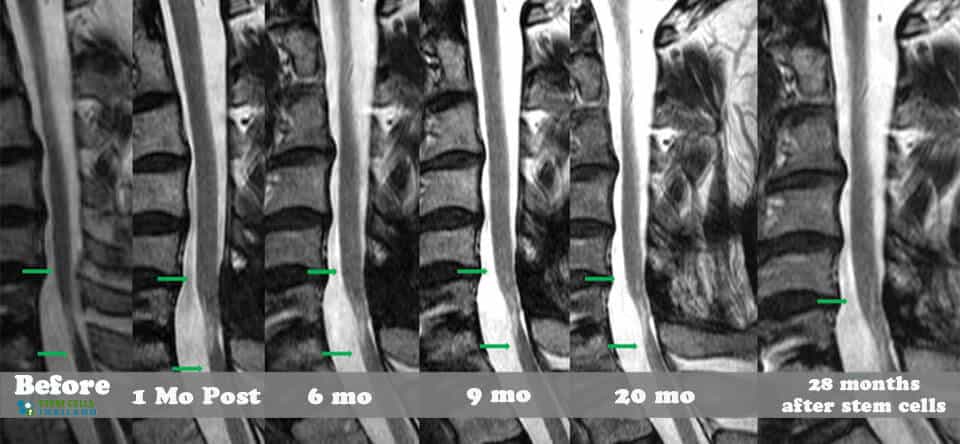

組織、軟骨或韌帶的新?lián)p傷對干細(xì)胞治療的反應(yīng)要好得多。治療后的康復(fù)需要大量的奉獻(xiàn)和康復(fù)訓(xùn)練。初次治療后約2-3個月,身體改善明顯,且效果是永久性的。[2]

干細(xì)胞治療價格和費(fèi)用脊柱損傷的情況取決于損傷的嚴(yán)重程度和所需的治療方案。為了符合脊柱治療方案的資格并獲得固定價格的免費(fèi)治療計劃,醫(yī)生需要通過您的初級保健醫(yī)生或最近的MRI、CT 掃描和臨床診斷來了解您的需求。